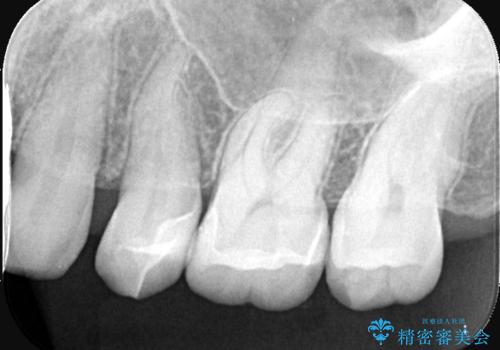

左上5番目の歯の側面に実質欠損を認め、隣の6番目の歯にも虫歯を認めたため両歯ともセラミックインレーでの治療となりました。

左上5番遠心に実質欠損を認め、さらに5番と6番の隣接面にもカリエスを認めました。6番の咬合面には、元々コンポジットレジン修復が施されており、劣化がみられたのでその部分も含め修復することとなりました。